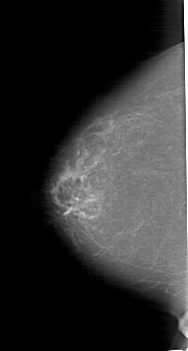

A_1170_1.RIGHT_MLO

RIGHT_MLO LINES 6466 PIXELS_PER_LINE 3196 BITS_PER_PIXEL 12 RESOLUTION 43.5 OVERLAY

FILE: A_1170_1.RIGHT_MLO.OVERLAY

TOTAL_ABNORMALITIES 1

ABNORMALITY 1

LESION_TYPE MASS SHAPE LOBULATED MARGINS CIRCUMSCRIBED

ASSESSMENT 4

SUBTLETY 4

PATHOLOGY BENIGN